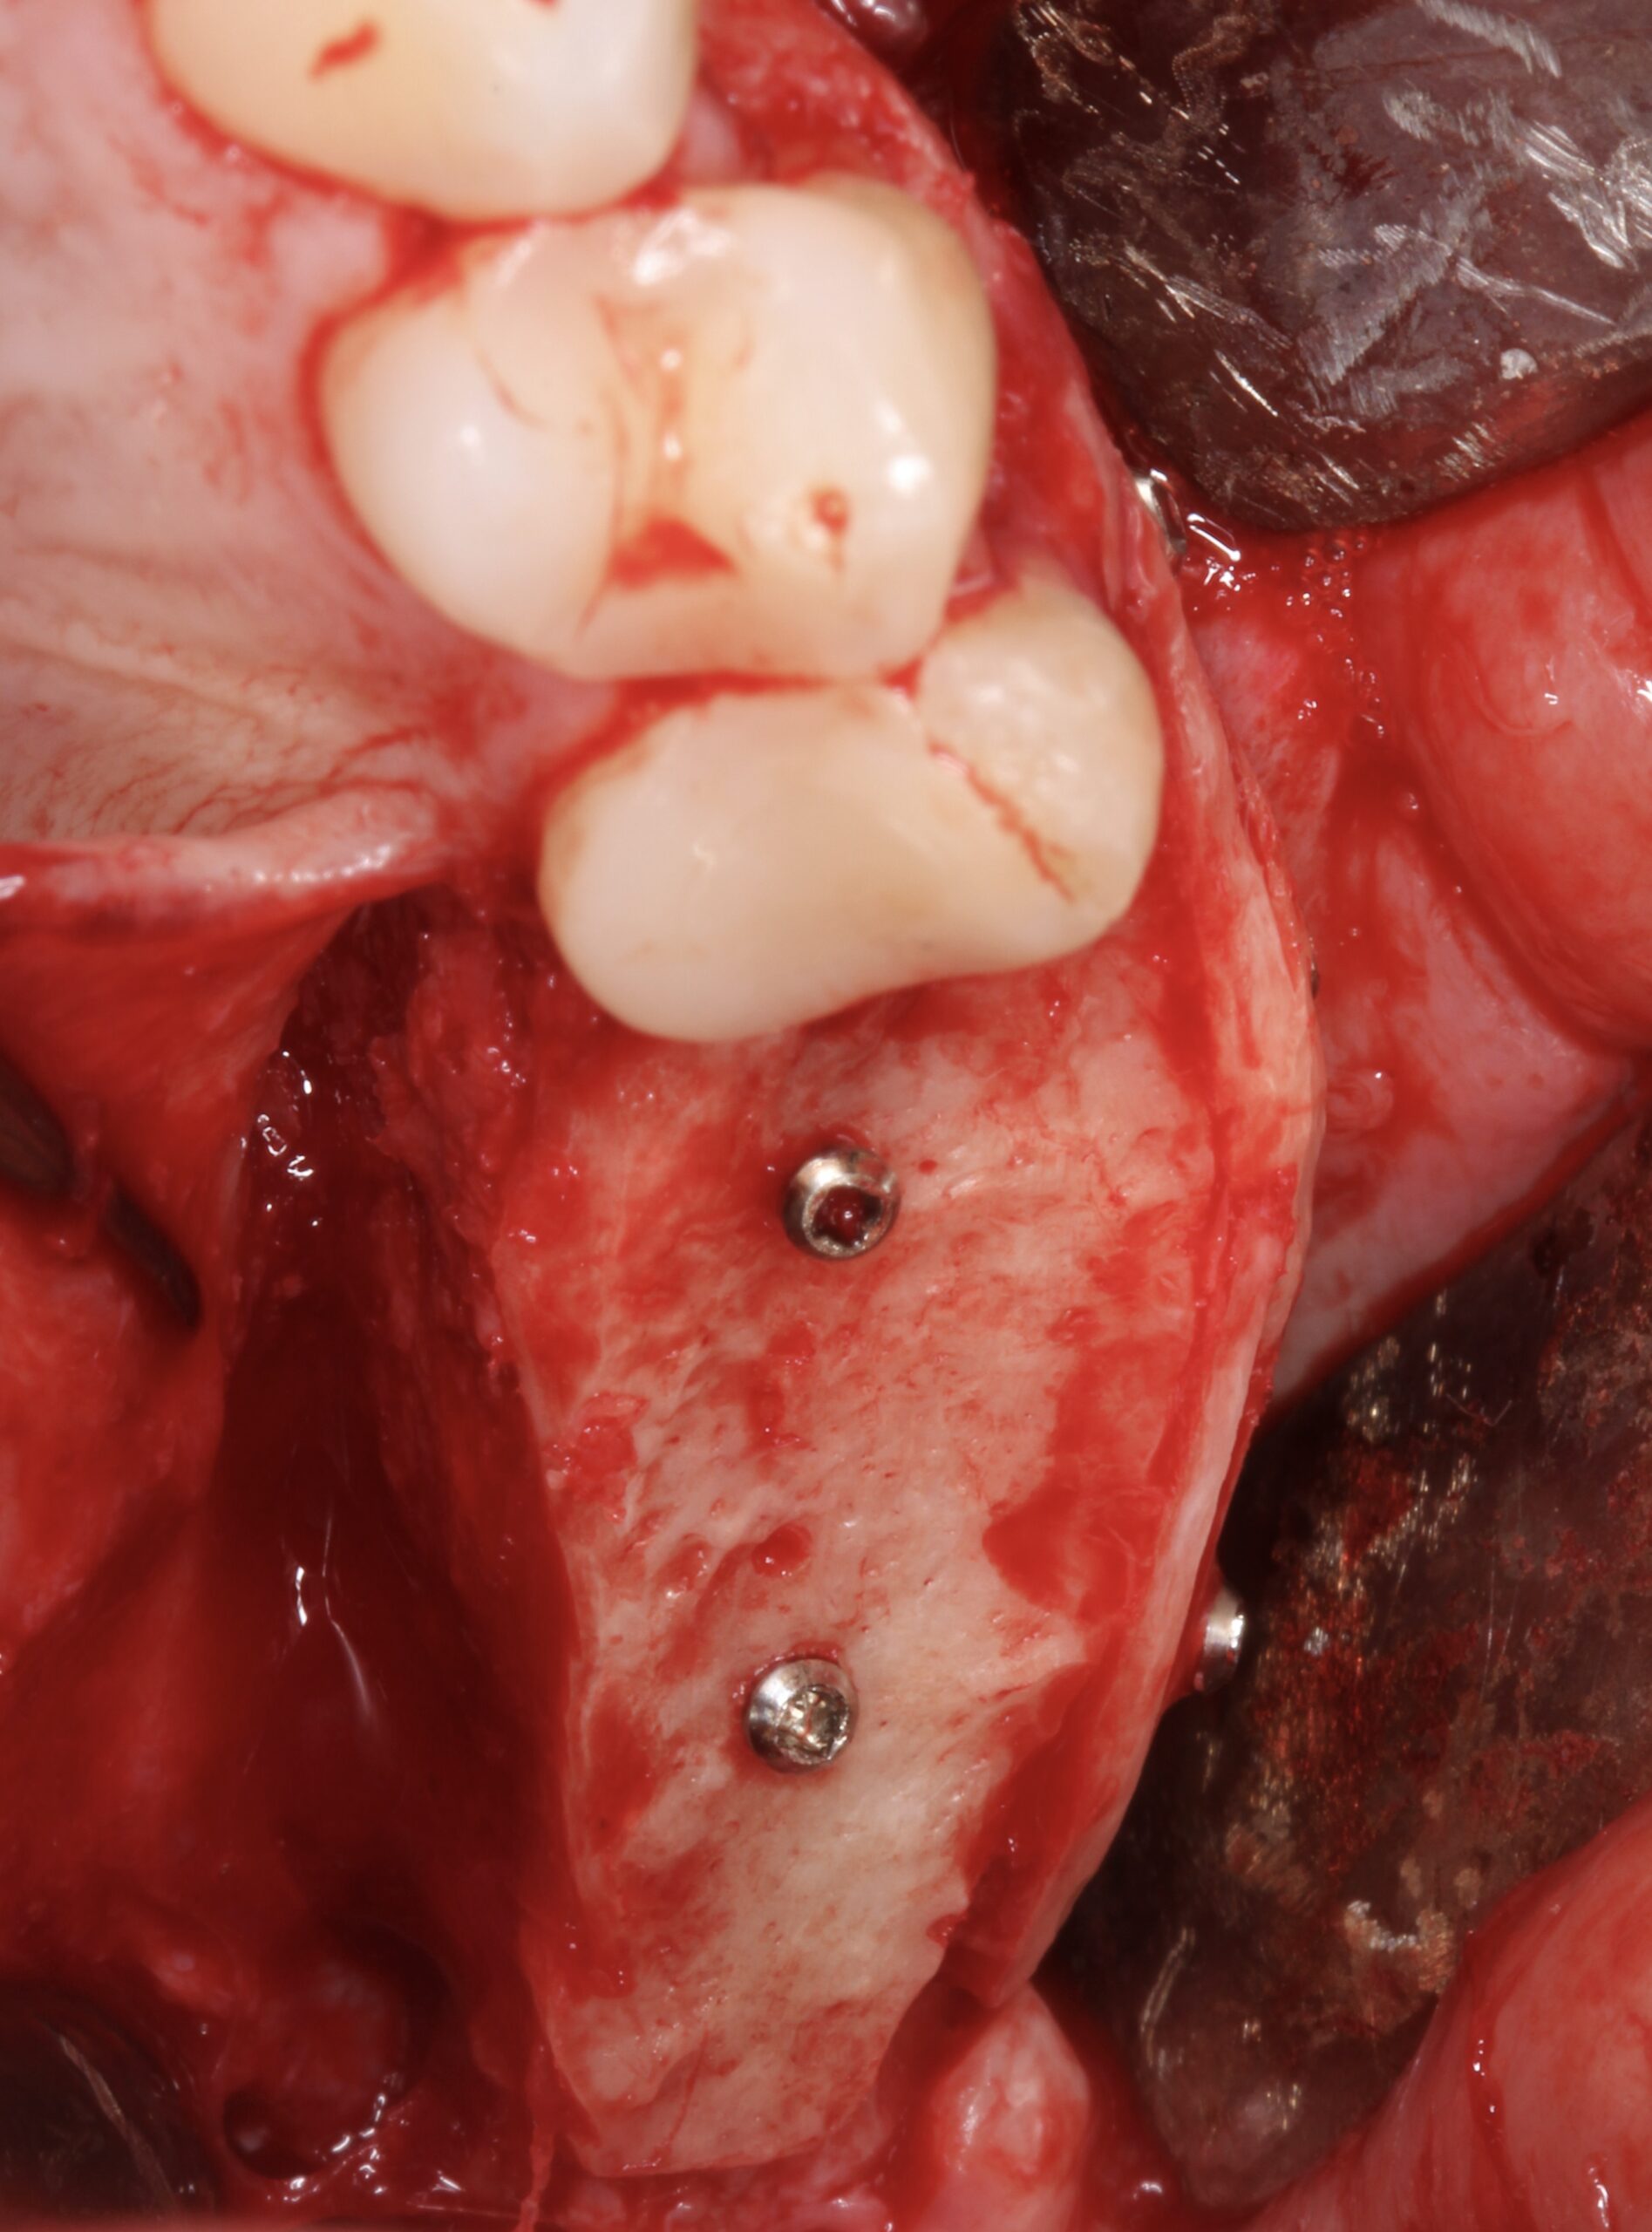

Figure 5.

A split bone block was fixed by screws at the coronal aspect of the alveolar ridge from peak to peak.